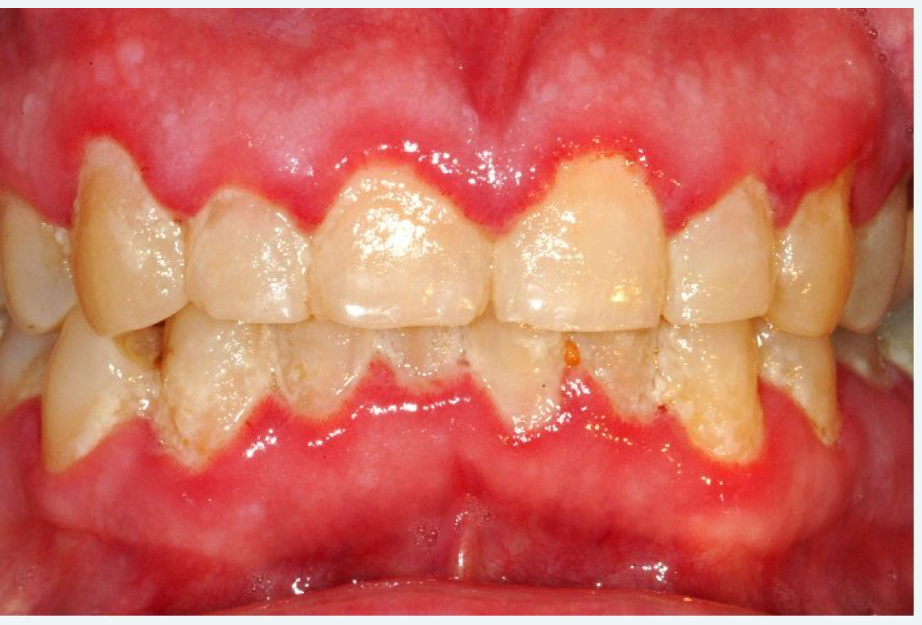

Caractéristiques Cliniques d’une Gencive Saine

Contour

Il suit la configuration des collets anatomiques. Le rebord marginal doit se terminer en biseau pointu.

Couleur

Habituellement rose pâle, mais elle dépend aussi de l’épaisseur de l’épithélium, de la concentration des vaisseaux sub-épithéliaux, du degré de kératinisation et de la présence de pigments de mélanine.

Consistance

Elle est ferme au niveau de la gencive attachée, inamovible par rapport au plan osseux sous-jacent, souple au niveau de la gencive libre ce qui la différencie de la muqueuse alvéolaire qui est lâche.

Texture

La gencive attachée vestibulaire ainsi que le centre des papilles présentent un aspect piqueté en peau d’orange qui semble être lié à :

- l’aspect histologique des crêtes épithéliales de l’interface épithélium-tissu conjonctif ;

- l’organisation du réseau fibrillaire et/ou

- au degré de kératinisation.

Cet aspect disparaît avec l’inflammation.

Volume

Une gencive saine présente un volume moyen qui maintient une hauteur physiologique de la gencive libre de 0,5 à 2 mm, ainsi qu’une épaisseur de 1 à 2 mm mais qui diffère d’un individu à l’autre et selon les endroits dans la même cavité buccale.